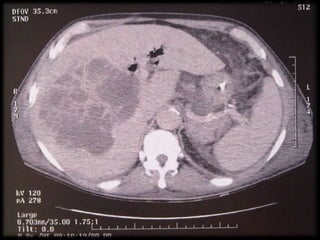

EXAME SENSIBILIDADE %

Ecografia Abdominal 90

Tomografia Computadorizada 95

 Percutânea ( US / TC )